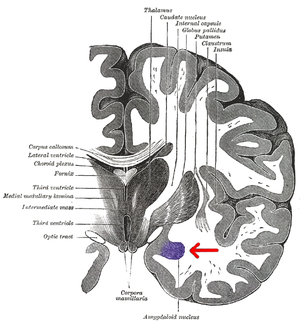

Subdivision of the amygdala

Coronal section of brain through intermediate mass of third ventricle. Amygdala is shown in purple.